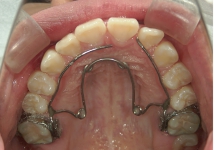

クワドヘリックス(QH)

上顎骨の横幅を広げる効果があり、上顎の幅が狭い時や、歯の生えるスペースが足りない時に使用します。症例2の場合、内側に入っていた左上2番が、装置に押し出されて正常な位置に移動しました。